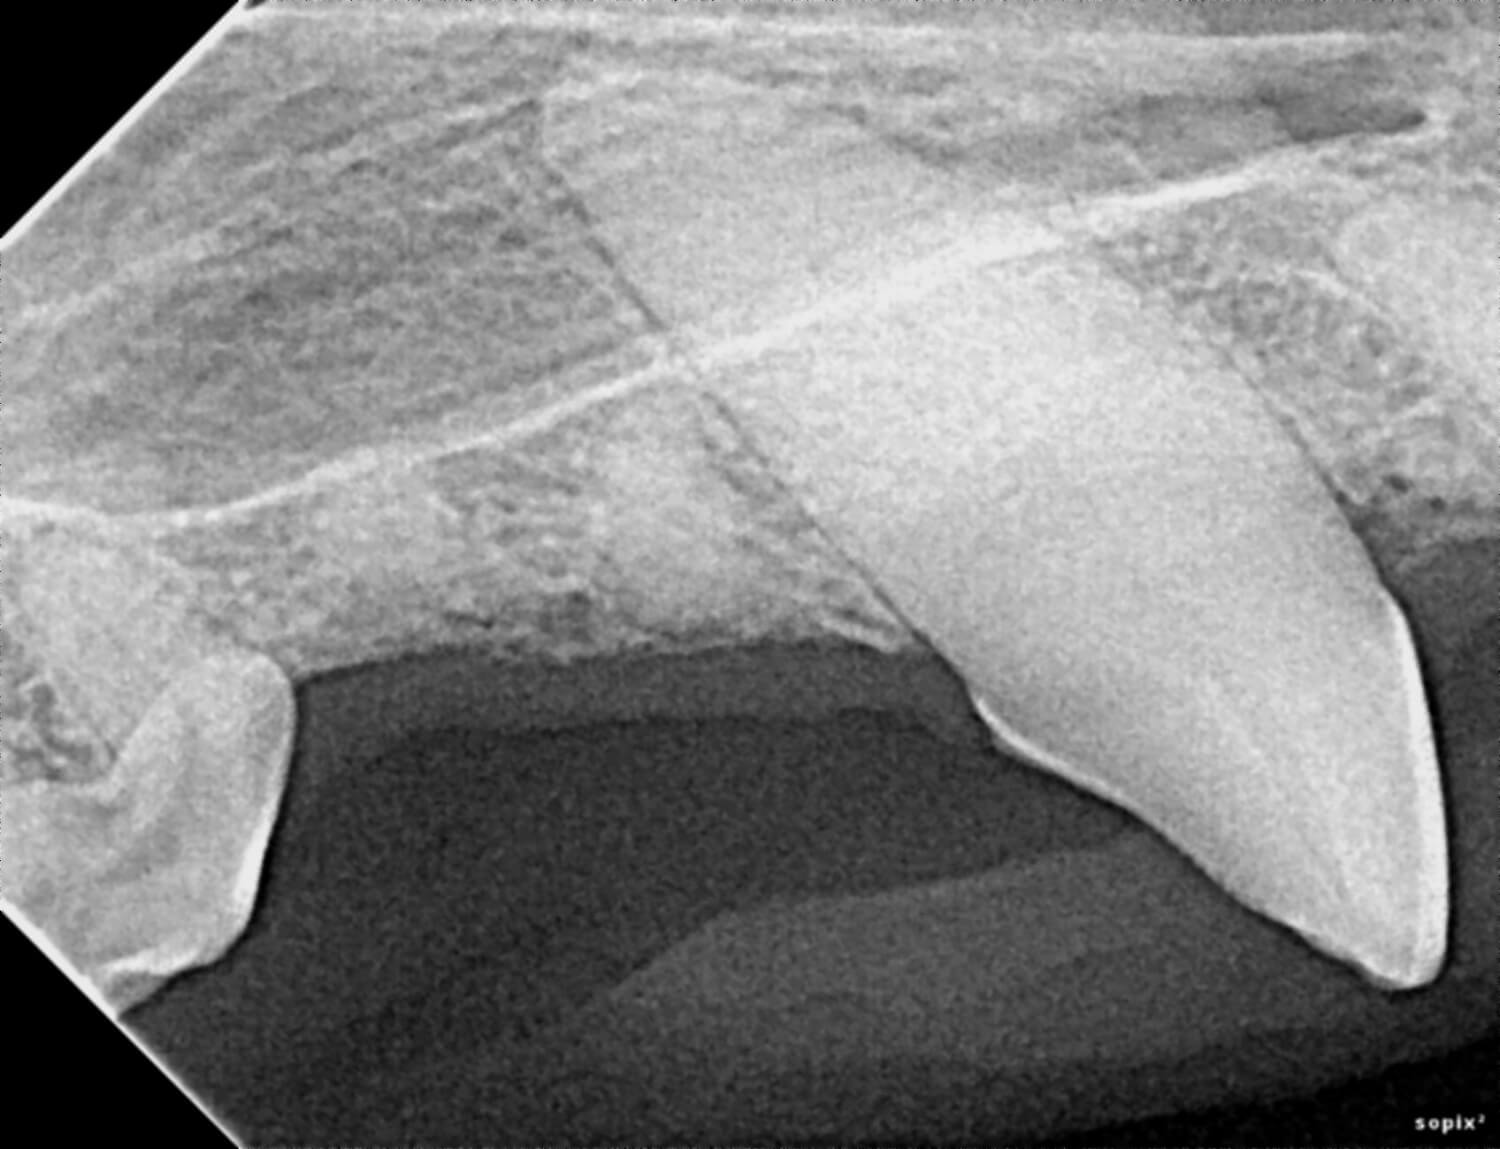

Our veterinarians use digital radiology to detect conditions such as tooth root abscesses, oral tumors, jaw fractures, and hidden dental disease. Early diagnosis enables timely treatment, reducing pain and preventing advanced dental complications.

Digital radiology plays a vital role in preventive health and advanced diagnosis for pets. Dental and oral conditions are often hidden below the gumline, where physical exams cannot detect them.

This imaging can reveal issues such as periodontal disease, infections, tooth resorption, and bone loss before they cause noticeable pain or lasting damage. Prompt diagnosis allows our team to provide targeted treatments that keep your pet comfortable and healthy.

Precise imaging guides our veterinarians in planning surgical or dental procedures for maximum safety and effectiveness. Detailed X-rays also support ongoing monitoring for chronic conditions.